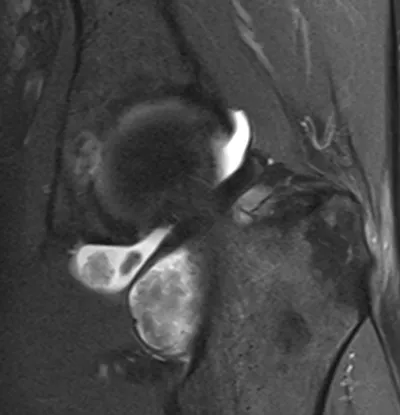

This collection contains 1 radiology images related to synovitis, including various imaging modalities such as X-rays, MRIs, CT scans, and ultrasound images commonly used in medical diagnosis and education.